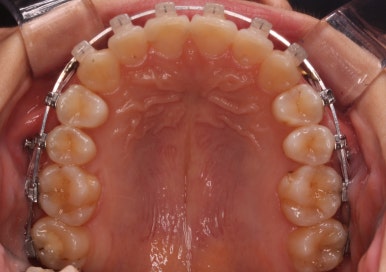

몇 달간의 마무리과정을 거치고 드디어 장치를 제거하였습니다.

위아래 앞니는 다시 틀어지지 말라고 유지철사를 붙였습니다.

위에는 탈착이 가능한 유지장치도 사용합니다. 2중으로 안전장치를 하는 것이죠.

치아는 매우 가지런해졌고, 과개교합도 개선이 되었으며 뻐드러진 앞니 각도도 정상적으로 회복이 되었습니다.